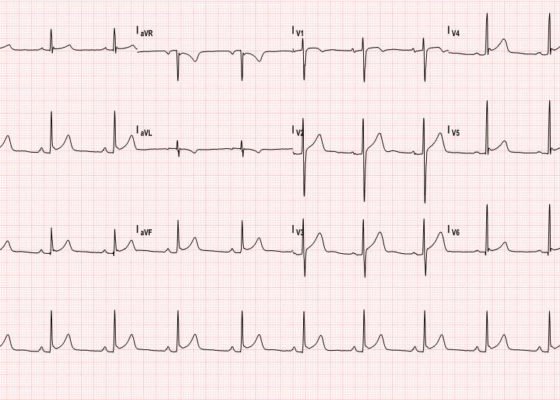

Acute Pericarditis: Electrocardiogram

DOI: https://doi.org/10.21980/J8059QThe ECG shows diffuse ST- elevation. The patient also has mild PR-depression, most notably in the inferior and lateral leads. The patient also has minimal PR elevation in lead aVR. The patient was diagnosed with acute pericarditis (ECG stage 1).